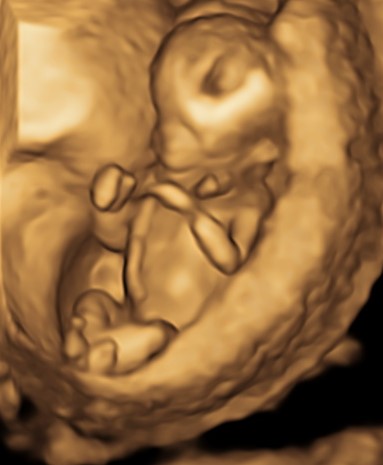

Comincia una fase completamente nuova dove invece di un fagiolino abbiamo a che fare con un piccolo tesoro che salta, saluta e si mostra in tutto il suo splendore a mamma e papà che non possono che rimanere affascinati da come in quei 4/5 centimetri possano concentrarsi così tanto amore e così tanta perfezione.

In questi 4/5 centimetri la risoluzione degli apparecchi moderni riesce a fare una prima valutazione morfologica, per vedere che ci siano tutti i “necessori” ed eventualmente anche accessori: cercando è possibile evidenziare il tubercolo genitale (sempre che il piccolo decida di essere collaborante e mostrare le proprie grazie). Si chiama così perché clitoride e pisellino hanno le stesse dimensioni a questa epoca, ma è possibile riconoscerli in base all’angolo rispetto al corpo: parallelo al corpo per le signorine, verso l’alto per i maschietti. Attenzione però la sensibilità, ovvero quanto ci azzecchiamo, è intorno al 60%.

La parte morfologica è molto importante, riusciamo a studiare l’estremo cefalico – a questa epoca il cervello fetale è molto semplice – , il massiccio facciale con occhi, naso bocca, le orecchie sono abbastanza facili da essere evidenziate. Nel torace oltre ai campi polmonari possiamo vedere il cuore battere ritmicamente e confermare la presenza delle quattro camere cardiache. Nell’addome riusciamo ad evidenziare lo stomaco e l’inserzione del cordone ombelicale. Si nota la presenza della vescica e del tubercolo genitale. Si possono esplorare tutti e quattro gli arti.

Per i genitori vedere sotto i propri occhi prendere forma il tesorino risulta una esperienza indimenticabile e impareggiabile al limite fra incredulità e la sorpresa come tutto sia già presente seppur in scala ridotta.